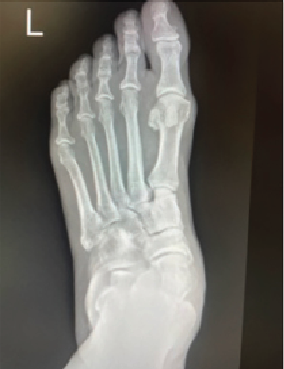

Implementing an Intermetatarsal Screw During Lapidus Arthrodesis

Arthrodesis of the first metatarsocuneiform joint has become a commonly performed procedure for patients with metatarsus primus elevatus, hallux valgus, hypermobility, arthritis of the first tarsometatarsal (TMT) joint, and in revisional hallux abducto valgus surgery.1–6

The technique discussed in this article includes the addition of an intermetatarsal screw as well as the application of a shear-strain graft to the arthrodesis site. Implementation of an intermetatarsal screw for the Lapidus procedure provides stress shielding across the metatarsal cuneiform, thereby increasing the likelihood of successful union, which can subsequently improve pain and functional outcomes.7